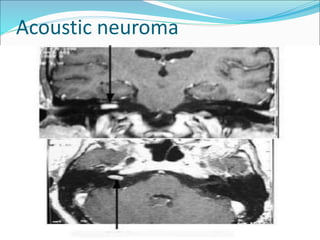

Acoustic neuroma

Penanganan dg pembedahan,

radioterapi atau observasi dg MRI

serial

Pilihan terapi tergantung umur, ukuran

tumor, kondisi medis pasien dan

pilihan pasien